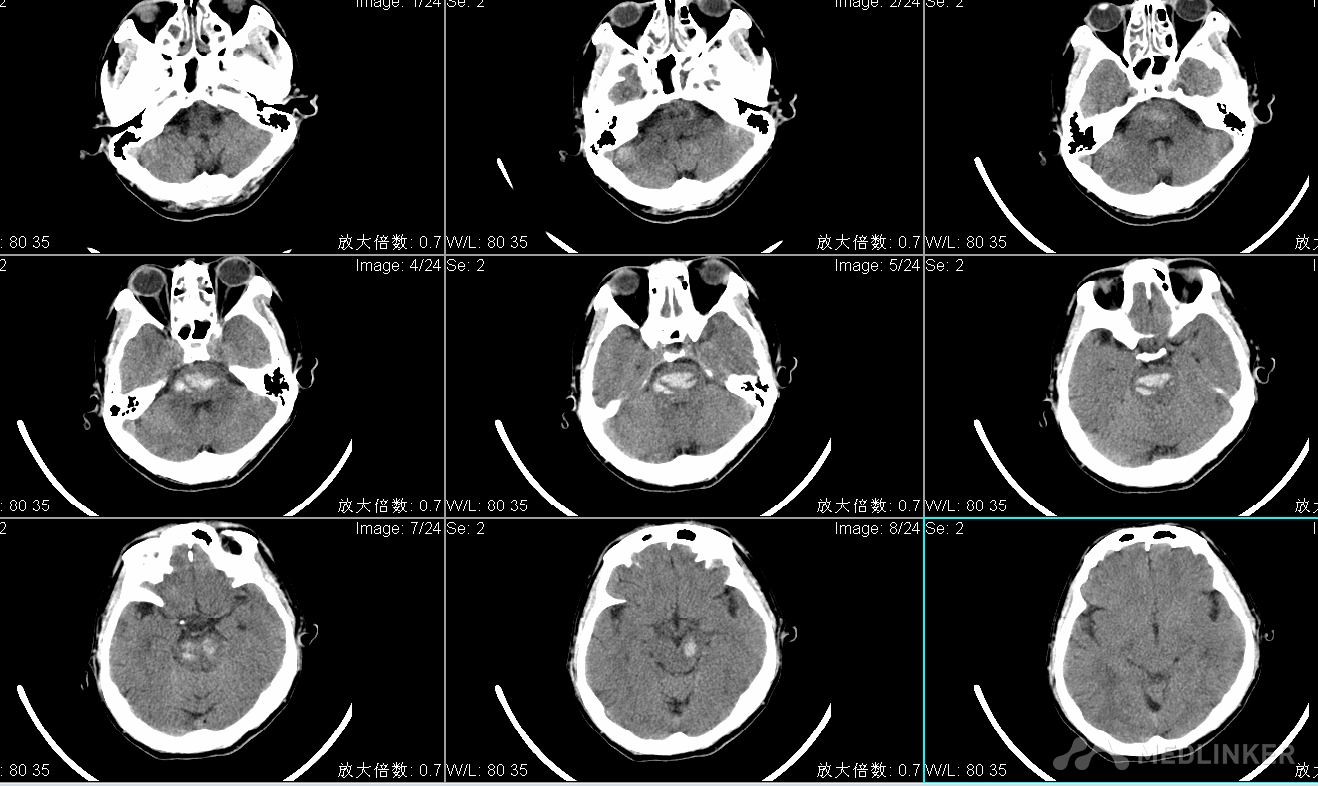

查体:T:36.8℃ P:61次/分R: 20次/分BP:181/101mmHg 昏迷状态,刺痛不睁眼,无发声,刺痛肢体可伸直,GCS4分,双侧瞳孔直径左:右=2:2mm,光反射迟钝,眼球居中位,额纹对称,颈软,肌张力高,腱反射(++),生理反射存在,双巴氏征(-)。头CT显示脑桥出血。

术前CT显示桥脑及中桥横贯性出血

骨窗范围 术后CT显示脑干血肿大部分清除 个人体会: 1.脑干出血造成损伤的主要原因:a、血肿的直接占位破坏效应;b、继发脑水肿;c、脑积水;d、凝血酶及氧化血红蛋白(血肿分解产物)造成的毒副作用,而手术可以清除大部分血肿,减少血肿的直接占位效应,并直接阻断继发性脑水肿的发生机制,打通脑脊液循环通路,改善患者的症状。 2.开颅手术的适应症与禁忌症: 适应症:患者处于昏迷状态,GCS8分以下,头颅CT显示脑干出血多田公式计算出血量大于5ml。 禁忌症:患者生命体征不稳定、脑疝形成时间较长、凝血障碍等。 3.手术入路的选择:脑干出血绝大数位于脑桥,由基底动脉的脑桥支破裂导致,偶见中脑出血,延髓出血极为罕见。中脑出血腹外侧者选择颞下入路,背侧者可选择Poppen入路;脑桥出血腹外侧略靠上者选择颞下入路,靠下者选择乙状窦后入路,背侧破入第四脑室者选择枕下后正中入路;延髓出血背侧者选择枕下后正中入路,腹外侧者选择远外侧入路; 4.术中尽量做到不牵拉脑组织或轻柔牵拉非脑干部位的脑组织;吸除血肿的过程中,显微镜直视下用小号吸引器缓慢进行,动作轻柔;整个手术操作在血肿腔内操作,不要越过血肿周围水肿带,血肿腔内的附壁小血块粘连紧密者,不必强行吸除; 5.术中止血是难点,对于静脉性出血,采用速记纱棉片压迫止血即可;对于动脉性出血,找准出血动脉,双极电量调低,轻轻电凝止血即可,整个手术过程术者一定要具备扎实的显微操作技巧; 6.术后人工硬脑膜严密修补缝合硬脑膜,逐层关颅,不留死腔,严防皮下积液,防止患者术后发热及颅内感染。